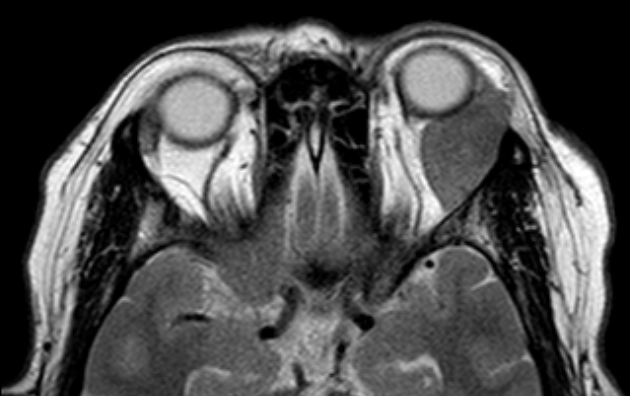

Typically found via imaging techniques such as CT scans or MRI. Can also be diagnosed through histology if a sample can be obtained.

The orbital infiltration is characterised by palpable, firm or rubbery mass